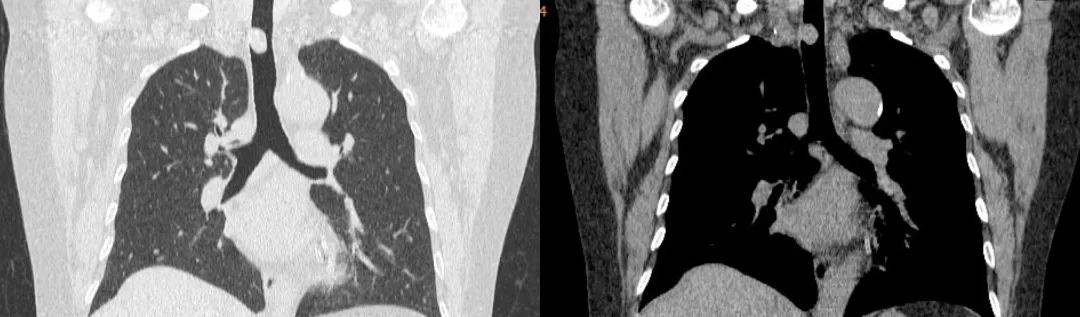

胸部CT:

胸部CT(冠状位)

四、影像学检查:表现为气管腔内的软组织密度肿块

表现为气管腔内的软组织密度肿块,多为偏心性,好发于气管后壁、气管软骨,低中度均匀强化,伴气管壁增厚,管腔不规则狭窄。有时可见气管旁淋巴结肿大,提示肿瘤转移可能。晚期可血行转移至肺、骨、脑、肝脏。